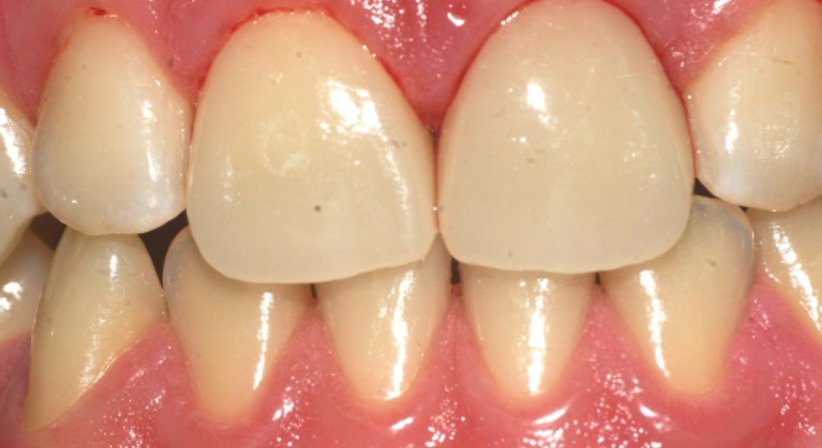

Zu Beginn wird die Karies bzw. die alte Füllung entfernt. Anschließend wird mit einer intraoralen Kamera eine dreidimensionale Aufnahme vom Zahn erstellt, der Patient sitzt hierbei bereits bequem auf dem Behandlungsstuhl - das Abformen, welches einst notwendig war, um einen defekten Zahn zu sanieren entfällt gänzlich. Im nächsten Schritt wird die Zahnrestauration am Bildschirm konstruiert (CAD), anschließend wird die Krone von der Schleifeinheit aus einem Keramikblock gefräst. Die Keramikblöcke sind in vielen verschiedenen Helligkeits- und Farbstufen verfügbar, sodass die Krone nicht nur hinsichtlich ihrer Dimensionen, sondern auch hinsichtlich ihrer Farbe perfekt an den Zahn angepasst werden kann. Nach einer Kontrolle der Passgenauigkeit und einem Glanzbrand wird die Krone zeitnah eingesetzt und ist von da an optisch nicht mehr von den natürlichen Zähnen zu unterscheiden.

- Kronen aus Keramik erfüllen höchste funktionelle Anforderungen und stabilisieren und schützen den Zahn optimal.

- Perfekte Ästhetik